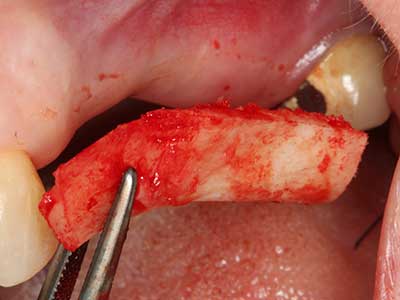

Piezo surgery has additional advantages when harvesting bone blocks. In addition to the high precision with osteotomy described above, the use of the thin saw tips specifically minimizes loss of material. Greater loss of material during harvesting can be expected with the thicker instrument tips, particularly when using Lindemann drills (Lakshmiganthan, Gokulanathan et al. 2012). The basal separation, which is necessary particularly for retromolar block transplants, is simplified by specially designed rectangular saws, with the result that piezo surgery is viewed as a precise, simple and safe procedure for harvesting retromolar bone blocks (Happe 2007) (Fig. 1-12).

Fig. 3: Basal separation of the block is easier with specially angled attachments.